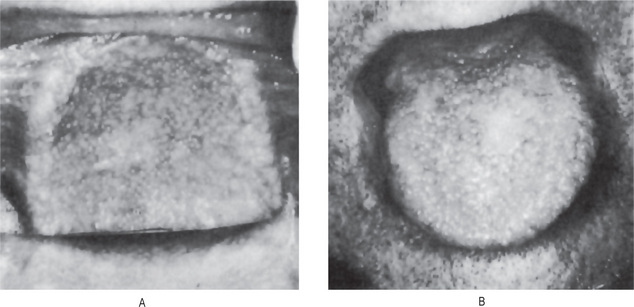

Porokeratosis of Mibelli is an uncommon genokeratosis characterized by faulty keratinization of the skin followed by atrophy. It appears to be inherited as a simple dominant characteristic, although many sporadic cases are known. There is no adequate documentation that the lesions of porokeratosis, despite the name of the disease, have their origin in the epidermal pores of sweat glands.

The majority of cases begin in early childhood but the progression of the lesions is generally exceedingly slow. It appears to occur in males with greater frequency than in females. The lesions themselves consist initially of crateriform keratotic papules which gradually enlarge to form elevated plaques ranging in size from a few millimeters to several centimeters. The lesions have a predilection for the extremities, particularly the hands and feet, as well as the shoulders, face and neck, and the genitalia. The nails commonly become thickened and ridged. The central portion of the lesions ultimately becomes atrophic, leaving permanent scarring. Epidermoid carcinoma has been reported developing in this atrophic skin. Lesions of the oral cavity are said to occur with considerable frequency in patients with this disease.